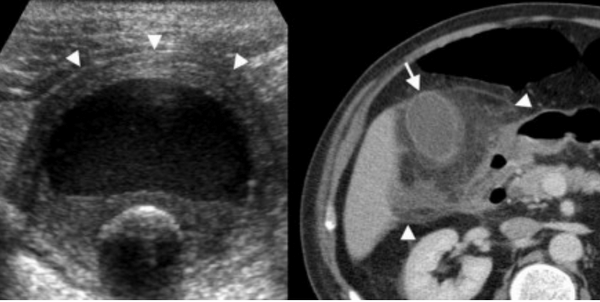

(Левый) У женщины 37 лет с острыми болями в правом верхнем квадранте живота на сагиттальном УЗ срезе желчного пузыря визуализируются отбрасывающие тень конкременты и сладж, а также опухолевидное дольчатое локальное утолщение стенки, прорастающее трансмурально.

(Правый) При КТ с контрастным усилением в режиме мульти планарной реконструкции в той же сагиттальной плоскости определяется полипоидное объемное образование стенки желчного пузыря, накапливающее контраст.

(Левый) При динамической МРТ в постгадолиниевую фазу в корональной плоскости наблюдается отсроченное прогрессирующее накопление контраста дольчатым полипоидным образованием, также виден дефект контрастной стенки желчного пузыря.

(Правый) У этого же пациента при МР холангиопанкреатографии определяются конкременты шейки и тела желчного пузыря и дольчатое полипоидное образование, пролабирующее в просвет желчного пузыря.